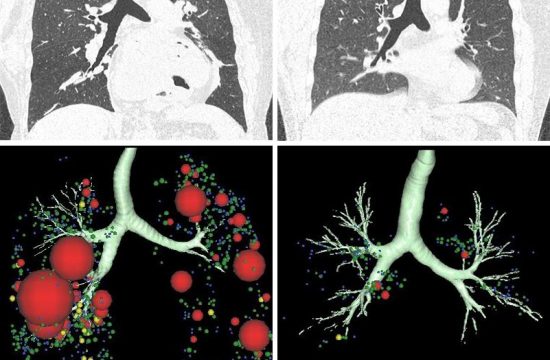

CT scans suggest possible lung destruction in some…

Clinicians have long thought that some people with asthma experience declines in their lung function, called fixed airflow obstruction (FAO), due to changes to their airways. Now, scientists at Hokkaido University and colleagues have found…